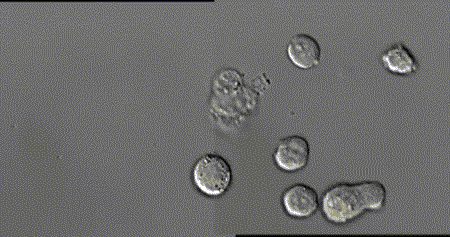

每个细胞毒性T细胞大约是人类头发直径的十分之一,它们在人体内不断巡逻,找出并杀死癌细胞或感染了危险病毒的细胞。

当T细胞(绿)发现癌细胞(蓝)时,通过分泌的毒素附着在癌细胞上,来检测、分辨正常细胞与癌细胞。

查明之后,T细胞(红)连接癌细胞(蓝),打破癌细胞外壁,向其表面引入毒性蛋白。

一旦细胞毒素(红)进入,癌细胞会逐渐衰弱、死亡。

而T细胞(绿)继续在人体内巡逻,寻找下一个目标。